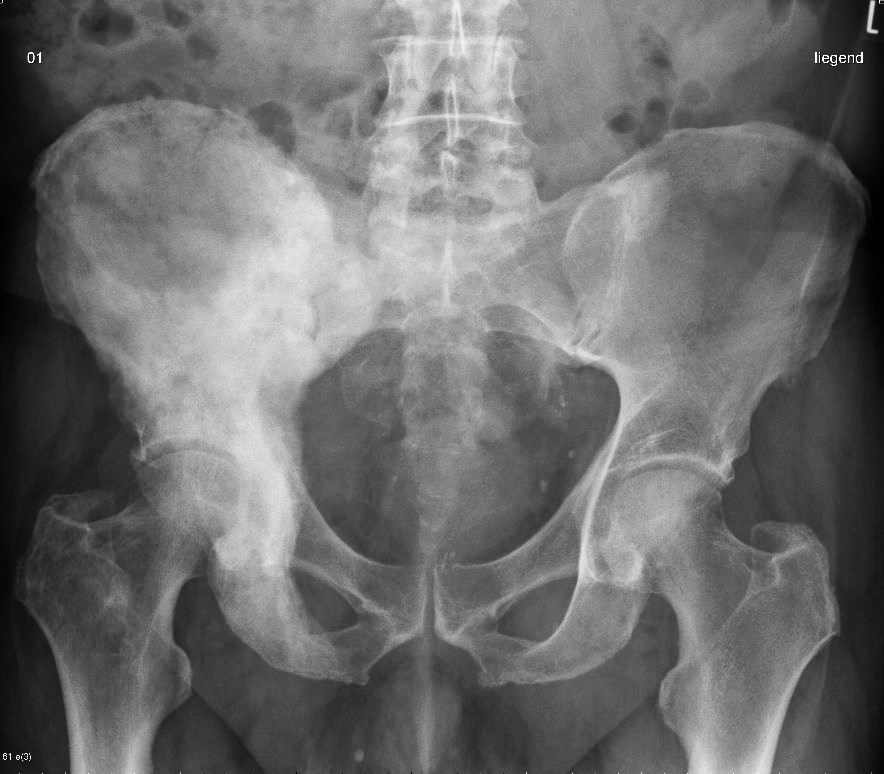

From radiopaedia.org

Paget disease Image Paget's Disease Dental Dental pulp in paget’s disease. Whereas paget’s disease may affect jaw bones and cementum of teeth, it also affects the dental pulp tissue, which lacks cellular structure with manifestation of. The dentist may recognize paget’s disease before either systemic manifestations or complications occur. Paget's disease (pd) is a chronic progressive disease of the bone characterized by abnormal. Suspicion may arise. Paget's Disease Dental.